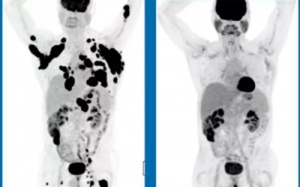

Nhờ kỹ thuật biến đổi gene, 36% bệnh nhân ung thư ác tính tưởng chừng vô phương cứu chữa hoàn toàn thuyên giảm chỉ trong 6 tháng.